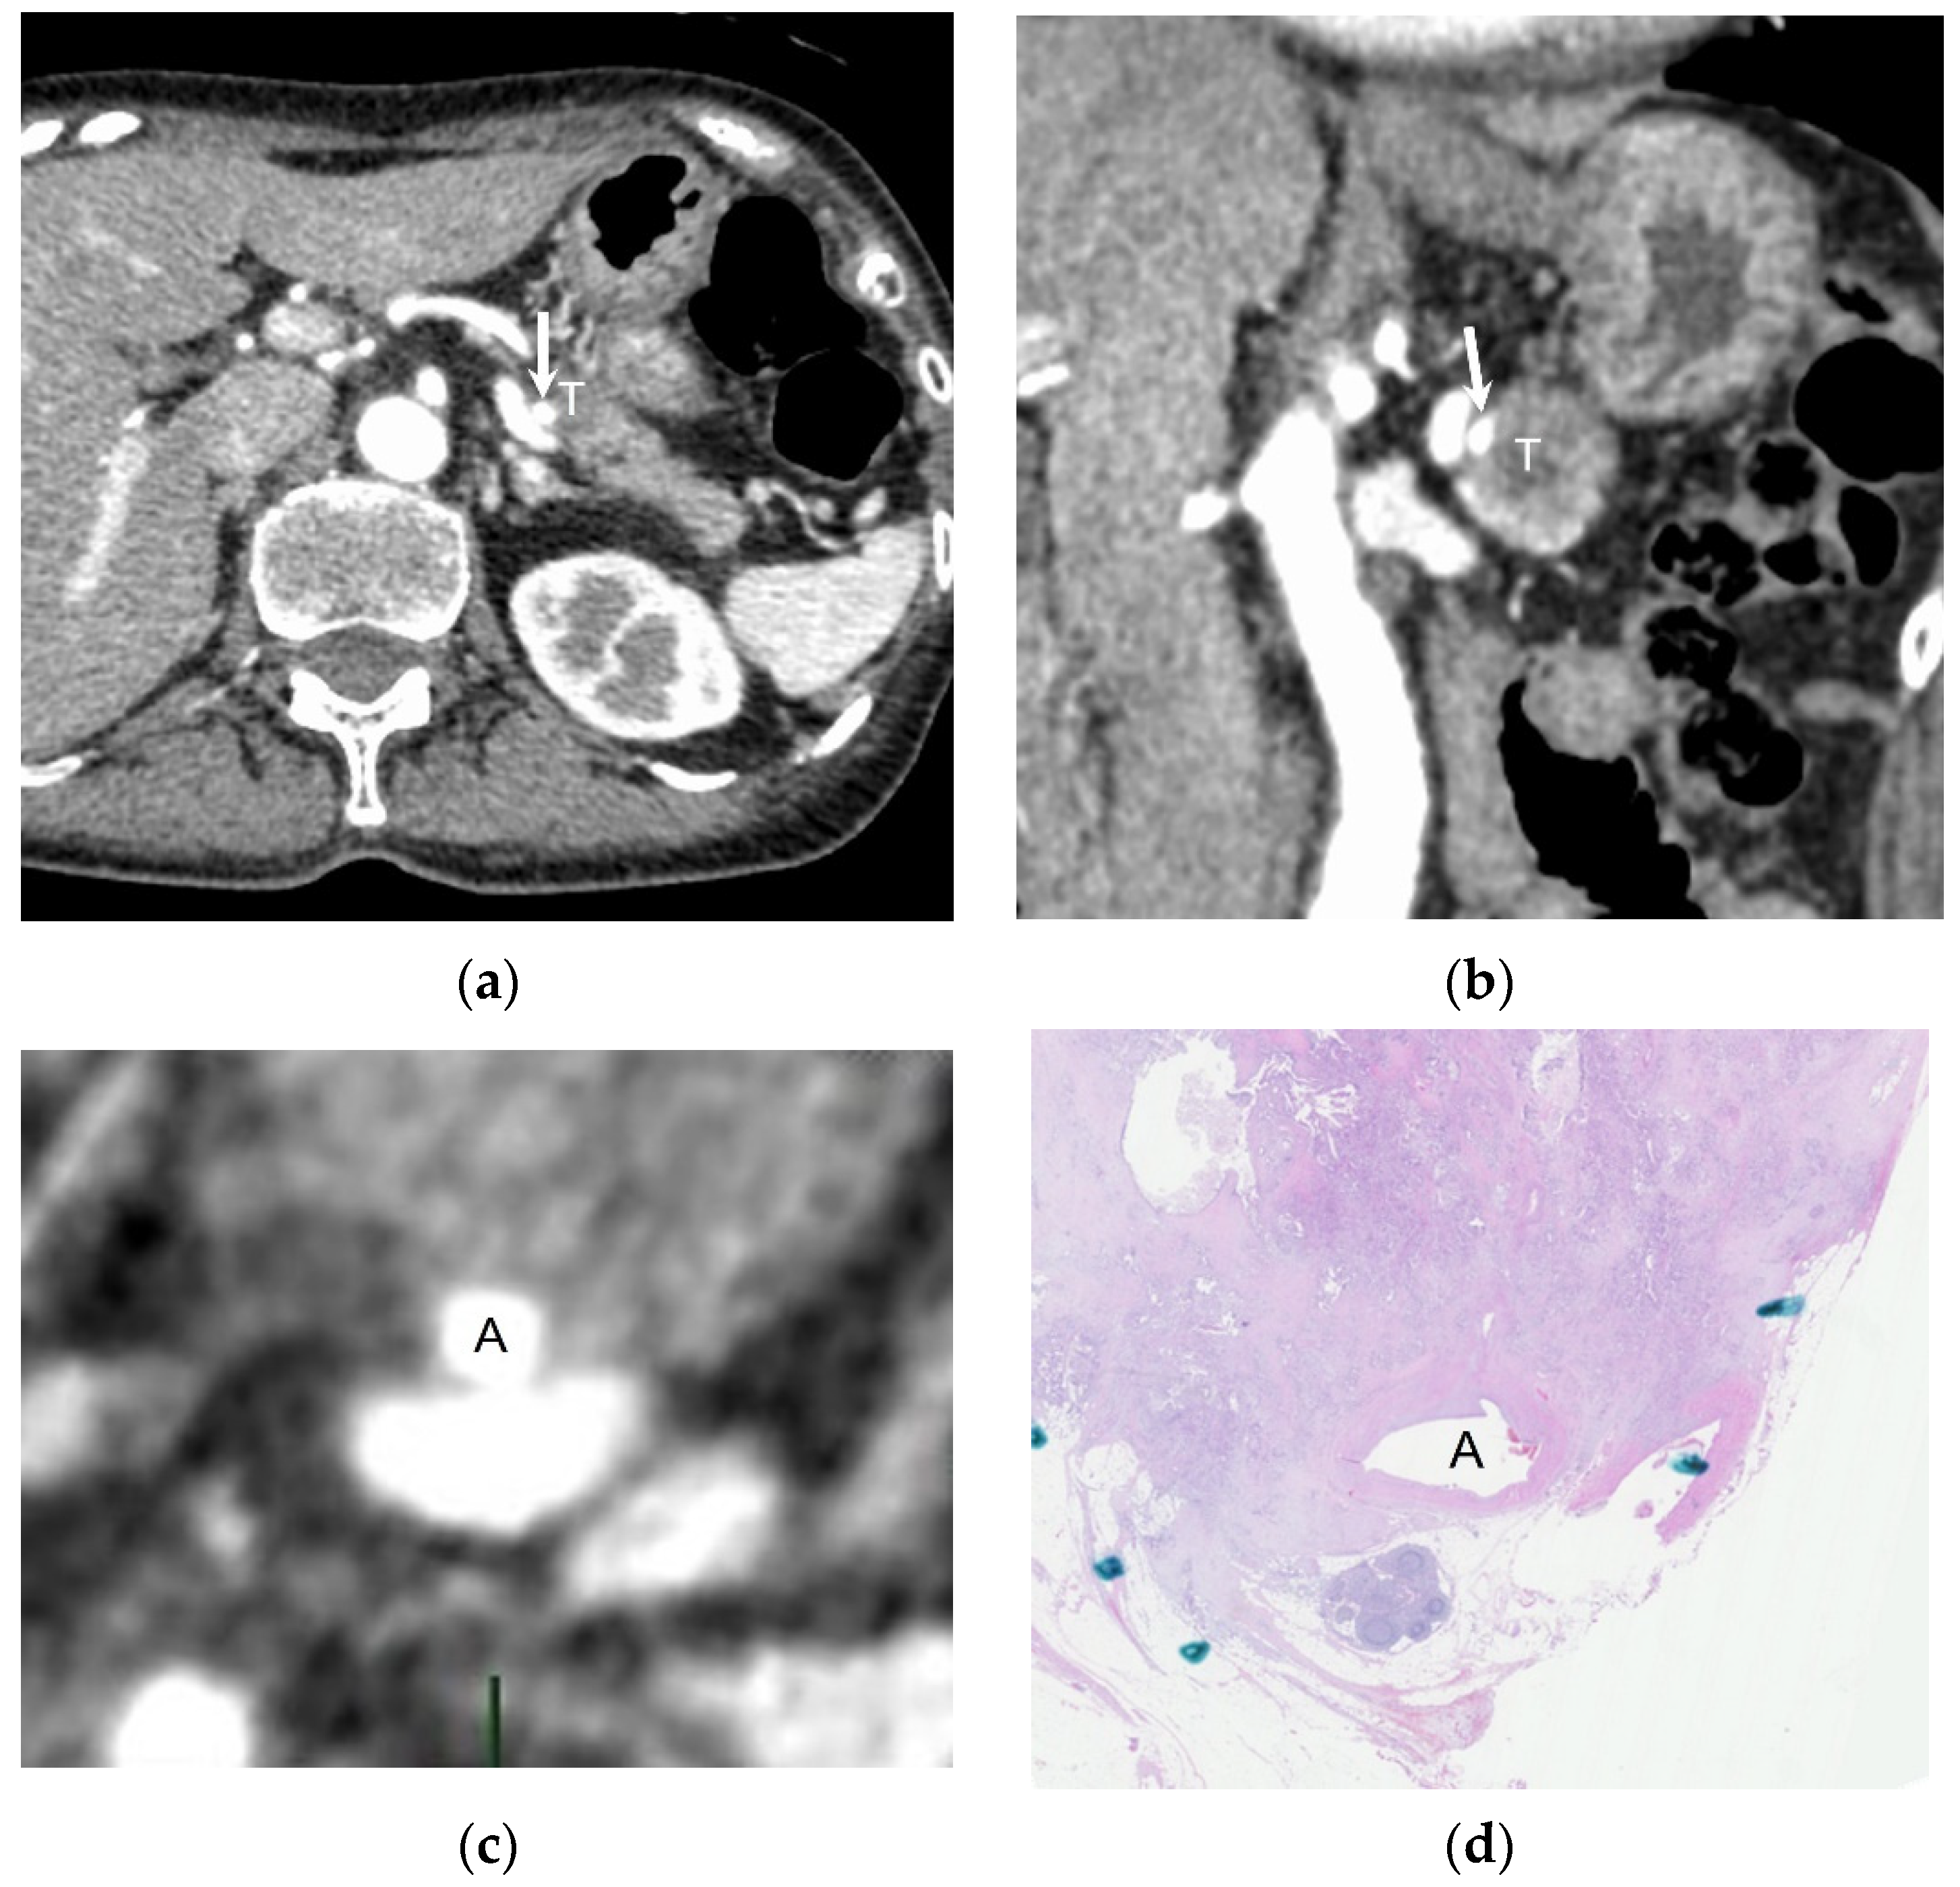

2.3. Creation of Perpendicular Reconstructed CT Images and Selection of Pathological Specimen

3.2. Pathological and Radiological Measurements of Solid Soft-Tissue Contact